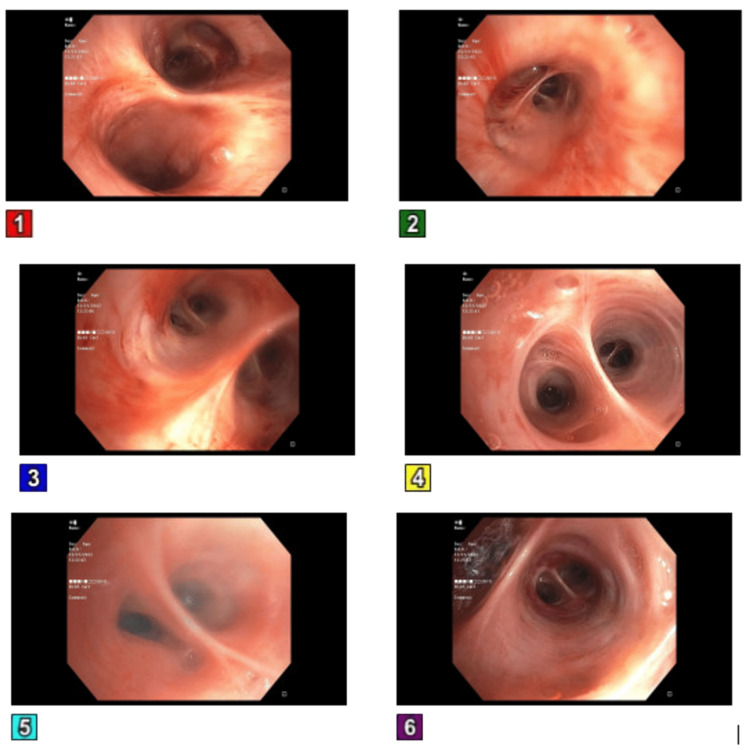

The patient was subsequently transferred to the intensive care unit (ICU) due to refractory hypoxic respiratory failure, necessitating intubation, as the administration of oxygen via nasal cannula proved ineffective in alleviating the persistent hypoxia and the patient displayed tachypnea. A bronchoscopy was done, which showed no active source of bleeding, and mucoid serosanguineous secretions were noted (Figure 3).